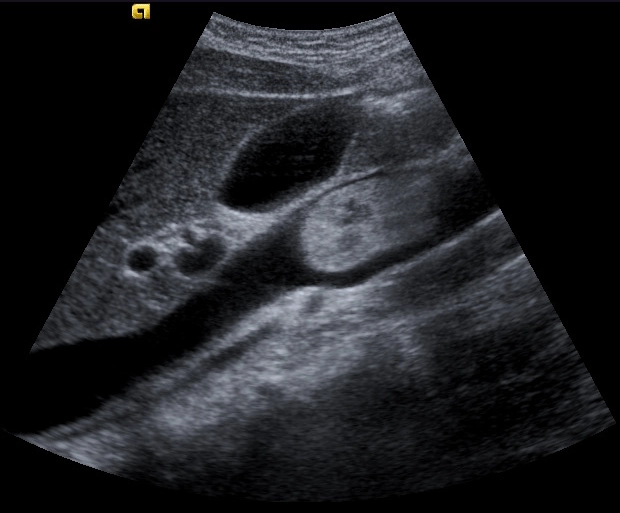

• Tăng áp lực tĩnh mạch cửa (Portal Hypertension)

• Huyết khối tĩnh mạch cửa (Portal vein thrombosis - PVT)

• Giãn mao mạch xoang gan (Hepatic peliosis)